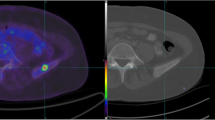

Nine bone metastases (spine 6, hip-bone 2, rib 1), demonstrated by increased signal intensity on T2 weighted STIR images (Fig. 8), were detected on WB-MRI in three patients. One spine lesion was missed on PET-CT while a rib lesion was missed on WB-MRI (Fig. 9).

Fifty-seven years-old patient with left femour metastasis. Coronal images T2W TSE STIR WB-MRI (A, A′), coronal PET image (B), axial T1W 3D FFE post-contrast image (C). Well defined hyperintense femour lesion on T2W TSE STIR images (arrowheads) demonstrates moderate metabolic uptake on PET image and significant contrast enhancement on T1W 3D FFE post-contrast image (arrow).

Fifty-nine years-old patient with left rib and bilateral iliac bone metastasis. Sagittal (A) and coronal (B) PET-CT fused images and corresponding PET images (C, D), axial T1W 3D FFE post-contrast images (E–H). Bilateral iliac metastases are evident on both PET-CT and T1W FFE post-contrast images (arrowheads) while the small left rib lesion visible on PET-CT (arrow), was not detectable on corresponding MR images (E, F).